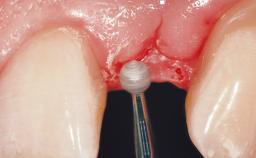

A 30-year-old female patient had lost tooth 21 and was referred to our clinic for consultation and treatment. Due to advanced apical infection, tooth 21 had been extracted two months earlier at another clinic and an acrylic-resin tooth had been bonded to the adjacent teeth. The patient desired implant treatment to avoid any damage to the adjacent natural teeth. While the patient had no history of any systemic disorder, she was a heavy smoker and exhibited medium to advanced periodontitis in the entire jaw. After the initial treatment to achieve a pocket probing depth of less than 4 mm and no bleeding on probing, a decrease in the height of the papillae mesial and distal to the extraction site and overall gingival recession were observed.